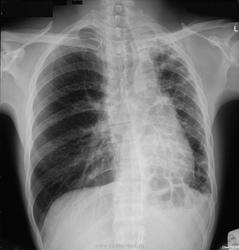

Рентгенодиагностика. Играет ведущую роль. Рентгенологические признаки кистозной гипоплазии можно разделить на три группы:

1. свидетельствующие о существовании множественных полостных образований в легких;

2. отражающие уменьшение органа или его части в объеме;

3. указывающие на наличие хронического воспалительного процесса в нижерасположенных участках бронхиального дерева.

К первой группе признаков относится наличие в области аномалии характерного ячеистого легочного рисунка, являющегося отражением множественных тонкостенных воздушных полостей. Наиболее часто ячеистый рисунок при кистозной гипоплазии наблюдается в области верхней доли правого легкого или же занимает все левое легкое.

Об уменьшении объема недоразвитой части легкого можно судить по смещению междолевой границы (в случае долевой гипоплазии) для средостения в сторону поражения, что более характерно для гипоплазии легкого, хотя может наблюдаться и при поражении доли.

Признаки третьей группы (пневмосклероз в зоне основного поражения или в соседних отделах легких, воспалительная инфильтрация в окружности кист, плевральные сращения, перибронхиальные и периваскулярные изменения) наблюдаются у относительно небольшой части наиболее тяжело больных с длительно и неблагоприятно протекающим нагноительным процессом и характерны скорее для приобретенной патологии, чем для кистозной гипоплазии легких.

Ячеистый рисунок отмечается практически у всех больных кистозной гипоплазией легких. Таким образом, на основании обзорных рентгенограмм можно лишь заподозрить наличие кистозной гипоплазии легкого, главным образом при наличии ячеистого легочного рисунка, разумеется, с учетом соответствующих клинических данных.